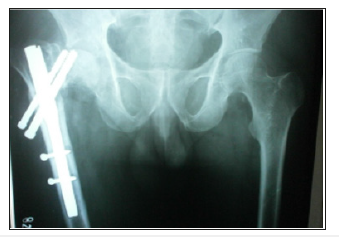

The most common complication encountered in our study was pain 29 cases (18.95%), delayed union 1 case (0.65%), malunion 8 cases (5.22%), non-union 3 cases (1.96%), Varus angulation 4 cases (2.61%), nail breakage 3 cases (1.96%), screw cut-out 3 cases (1.96%), Z effect 3 cases (1.96%), reverse Z effect 2 cases (1.30%) and avascular necrosis of femoral head 1 case (0.65%) (Figure 11a-11h) (Table 5). The pain at the fracture site were treated by oral analgesics. Delayed union case, associated with trochanteric fracture presented at 6 months, were treated with dynamization. Non-union cases were counselled for second surgical procedure with dynamic hip screw or hemiarthroplasty in case of intertrochanteric fracture and nail removal with compression plating with bone grafting in case of subtrochanteric fracture. The nail breakage cases were tracked regularly and offered nail removal and re-nailing. The cases with varus angulation got corrected in due course of bony remodelling after the nail removal. Screw cut-out, Z effect and reverse Z effect cases were under sentinel surveillance and were offered nail removal when the clinical and radiological signs of established fracture union. AVN of femoral head has been treated with cemented total hip replacement.

Figure 11g:Compression screw backout at 3 months with Varus collapse.

Figure 11h:Varus collapse with anti-rotation screw breakage at 6 months.